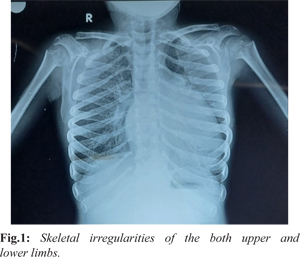

A 12-year-old female presented with complaints of exertional dyspnea persisting for two months, accompanied by pedal edema. The patient had normal intellectual development and an unremarkable past medical history. On examination, she exhibited characteristic morphological features including short stature, a short neck, and skeletal irregularities [Fig.1].